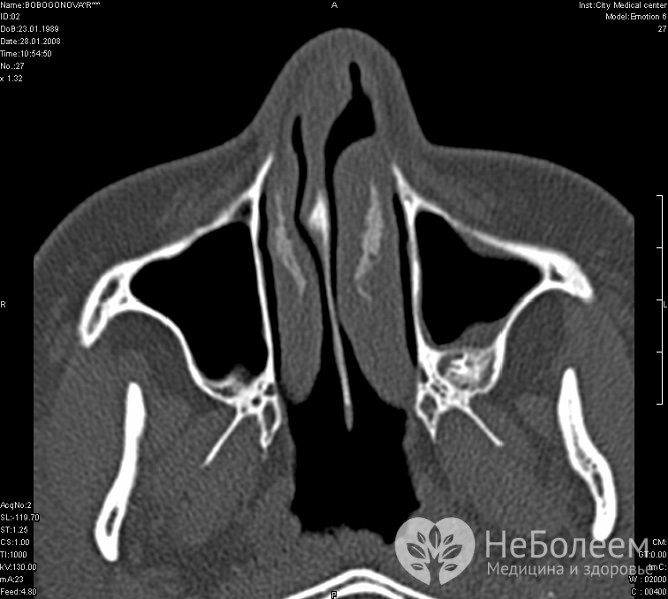

Лікар встановлює діагноз на підставі клінічної картини. До додаткових методів дослідження відноситься рентген навколоносових пазух у двох проекціях. Найбільш інформативною є комп’ютерна томографія.